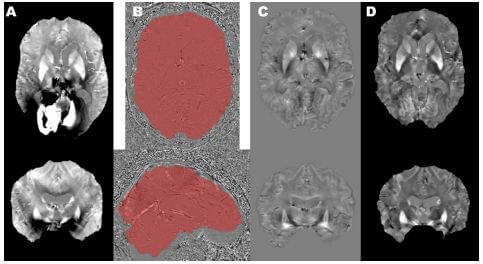

Studying iron accumulation using QSM in the SENIOR database

Using QSM to study iron accumulation in aging brains!

We previously reported that EOSC-Life (WP3) had awarded funding to the QSM4SENIOR project to perform ultra-high Field MRI Quantitative Susceptibility Mapping (QSM) reconstruction of a healthy brain-aging cohort (based on the SENIOR study) as part of the Digital Life Sciences Internal Call for Academia-Industry Collaboration.

Partners Ventio and NeuroSpin developed this project with the aim to reveal an innovative early biomarker for the pathological aging brain.

Now, the first project results detailing the accumulation of iron by using QSM in the SENIOR database will be presented as a poster at the upcoming QMR Lucca 2022 Joint Workshop on MR phase, magnetic susceptibility and electrical properties mapping on 16-19 October 2022 in Lucca, Italy.